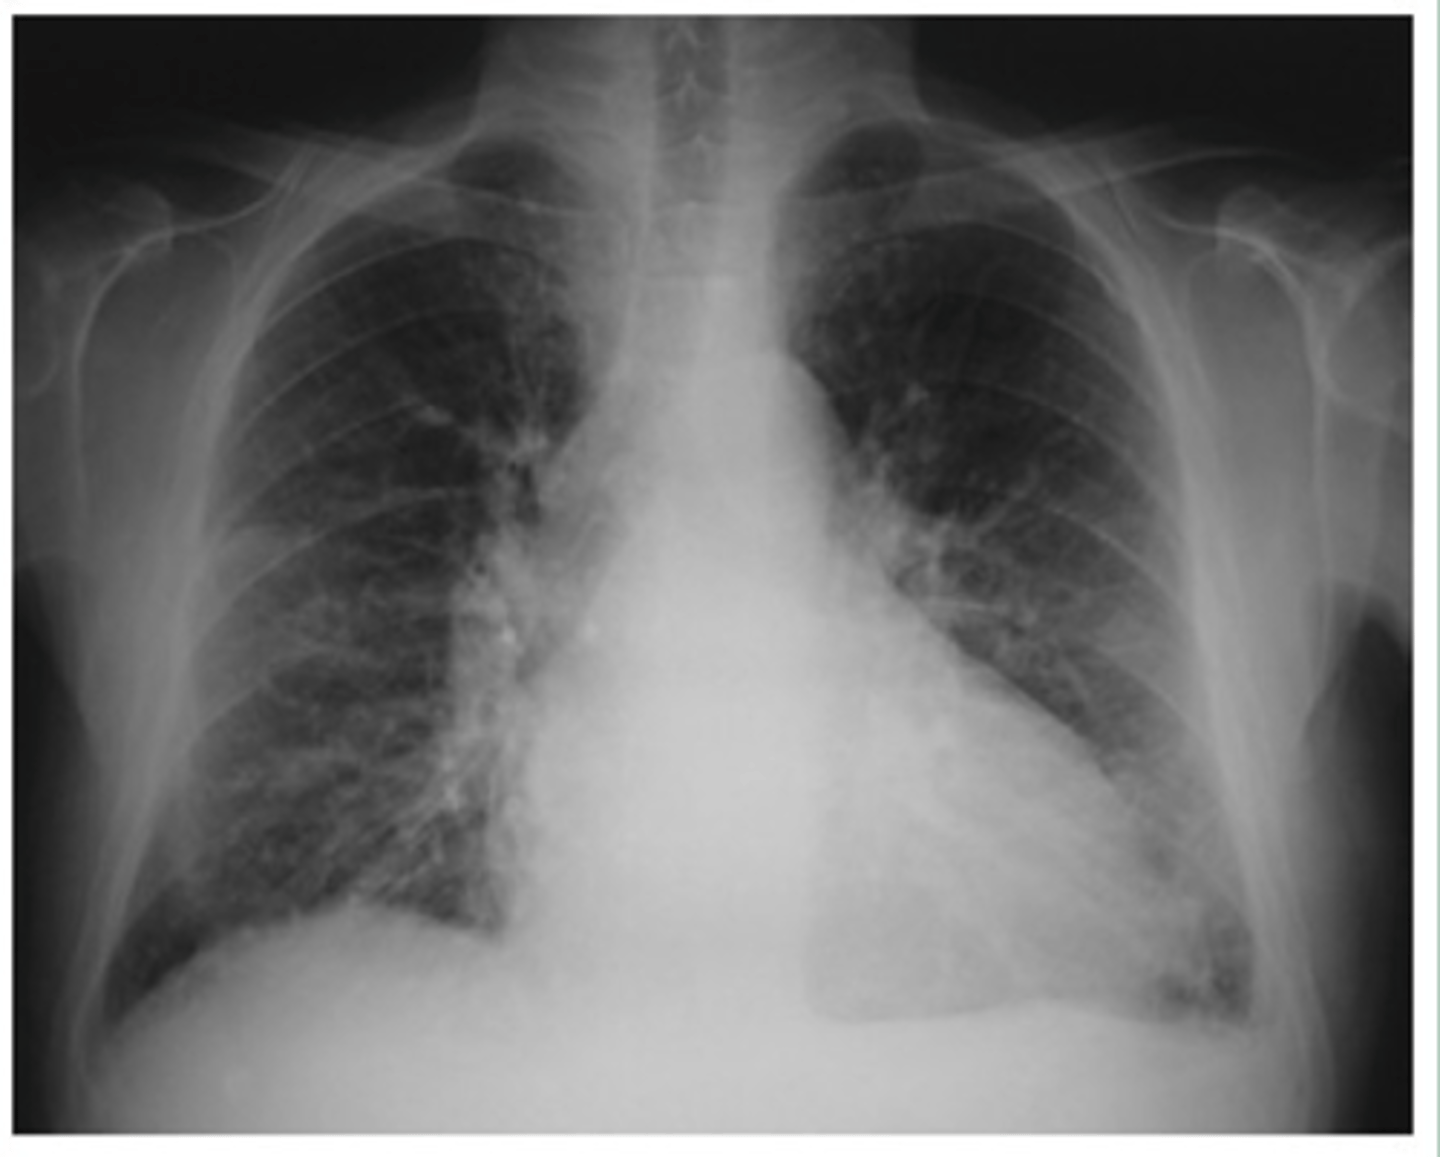

Moderate CHF with:

-redistribution of pulmonary vasculature (pulm vasculature should not be visible at all, esp in apices, but they are visible here)

-cardiomegaly and L sided pleural effusion

Dx - what kind of CHF is this?

<p>Dx - what kind of CHF is this?</p>

Mild to moderate CHF with redistribution of pulmonary vasculature, indistinct hila, mild cardiomegaly and Kerley B lines.

What signs on radiograph indicate CHF?

<p>What signs on radiograph indicate CHF?</p>